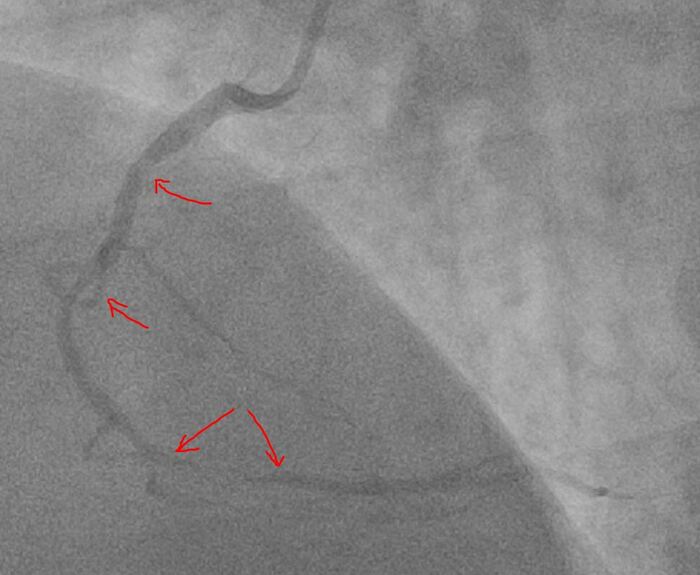

Стрелками показаны места сужений правой артерии

Правая коронарная артерия (ПКА): стеноз проксимального сегмента до 60%, протяженное поражение среднего сегмента со стенозированием до 70%, протяженное критическое поражение дистального сегмента со стенозированием >90% с замедлением дистального кровотока